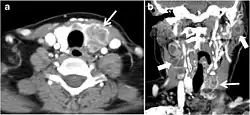

Fig. 11. Thyroid non-Hodgkin's large B-cell lymphoma in a 66-year-old female patient. an Axial enhanced neck CT scan demonstrates left thyroid lobe and isthmus homogeneously hypodense and minimally enhancing mass (white arrows). This lesion invades the prevertebral muscles (black arrows). Note the multiple enlarged level V lymph nodes (white arrowheads). b Post-treatment image shows significant reduction in size and mass effect of the left thyroid infiltrative mass, with almost complete resolution of the left cervical lymphadenopathy.[1] -

Fig. 12. Diffuse thyroid large B-cell lymphoma in a 79-year-old female patient. an Axial enhanced neck CT scan demonstrates a homogeneously hypodense and minimally enhancing large right thyroid solid mass (long white arrow) extending into the thyroid isthmus. It is encasing the right carotid artery (short white arrow) and displacing of the trachea and oesophagus to the left side.[1]